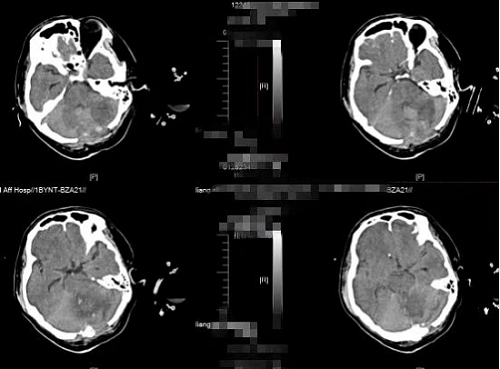

急诊科当即为患者开辟绿色通道,以全力赴抢救患者为先,及时为桂先生进行心肺复苏、气管插管、呼吸机辅助呼吸。神经外科二区伍贞宇医生在接到急诊科通知后,第一时间赶到急诊科评估病情,同时汇报神经外科二区科主任王鹏主任。该患者当时已处于深度昏迷状态,双侧瞳孔直径约2mm,对光反应消失,无自主呼吸及心跳。在协同急诊科抢救后患者心跳恢复,但仍无自主呼吸,病情仍十分危重,急诊行CT提示“左侧小脑半球脑出血并破入脑室,第四脑室及脑干受压,继发幕上脑室轻度脑积水,环池消失。”,脑内出血较前明显增多,脑疝形成,需立即进行手术。

图1术前CT

图2术后CT